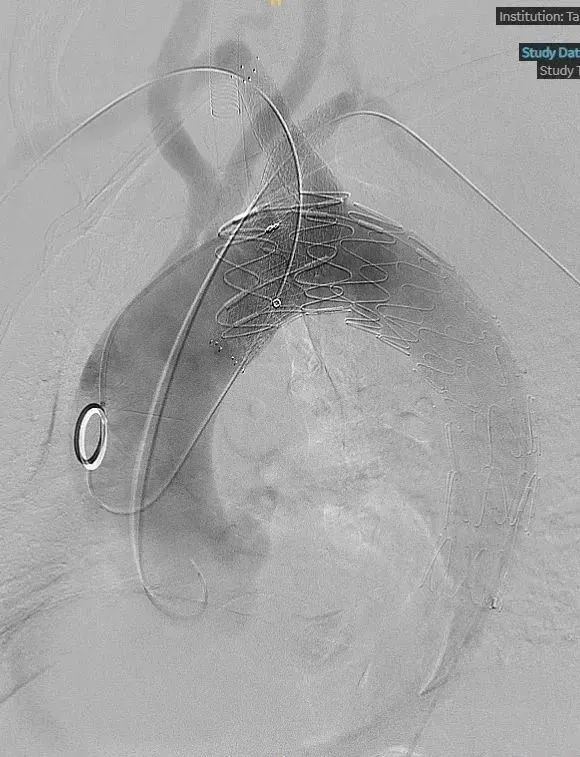

3.左侧股动脉穿刺,导丝导管到达主动脉部位,利用Fustar引导,造影定位,在右锁骨下动脉开口膨大处进行顺序穿刺。同时利用右锁骨下动脉导管冒烟定位,顺利穿刺并成功。

右锁骨下动脉置入Viabahn支架和Smart Control支架,左锁骨下动脉同样进行针刺开窗,最终造影情况良好。

术后造影复查,右侧迷走锁骨下动脉的烟囱支架角度平顺,血流通畅。